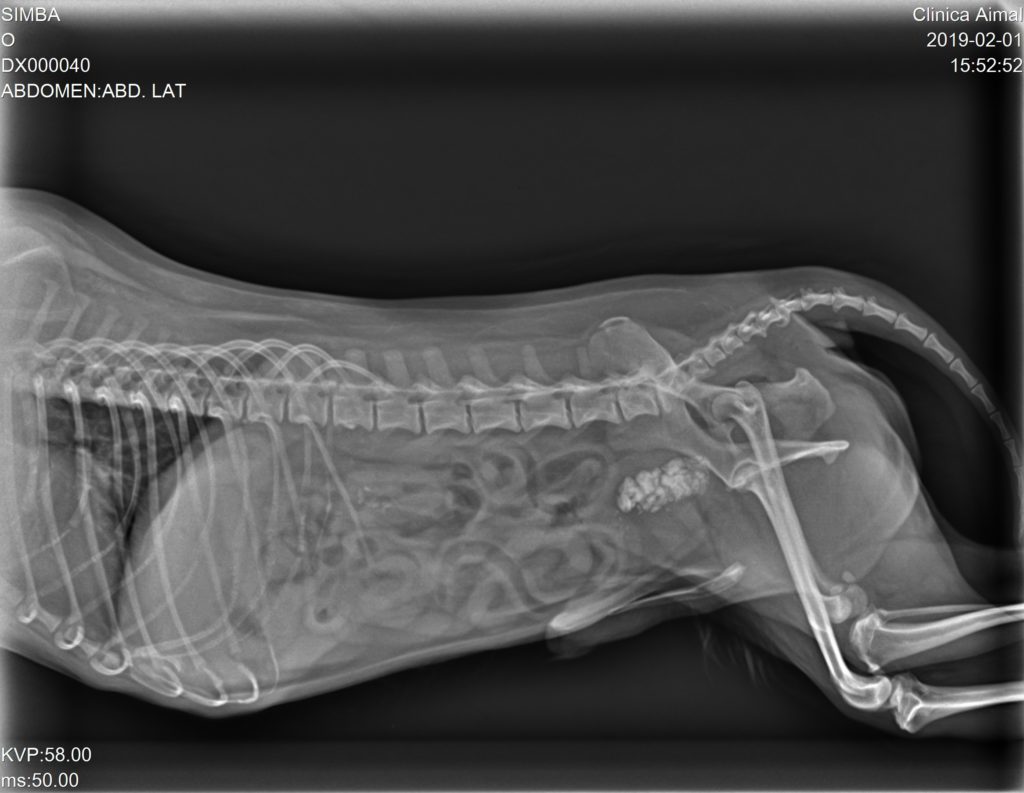

En la Rx pudimos observar gran cantidad de urolitos en la vejiga de la orina y uretra, depositándose en la parte más caudal del hueso peneano provocando una obstrucción incompleta:

Se sonda al animal para arrastrar mediante sonda y suero fisiológico a los cálculos de nuevo a la vejiga de la orina. Una vez realizado esto y contrastado mediante Rx, se pone tratamiento antibiótico, antiinflamatorio y se les cita para cirugía, en la cual se realizará una cistotomía y así retirar todos los cálculos.